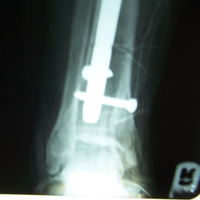

A male patient, aged 58 years had been diagnosed to have Closed comminuted fracture calcaneum . Closed reduction and percutaneous fixation done with CC Screw.

Pre-Operative

Post-Operative